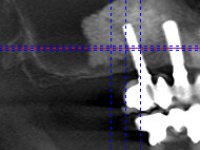

Realizada uma TAC, foi planificada a colocação de 6 implantes no maxilar superior. Foi decidida a colocação de dois implantes na zona dos incisivos centrais, dois implantes na zona dos caninos e dois na zona dos segundos pré-molares. A ausência de estrutura óssea na zona distal do primeiro quadrante implicava a realização de uma regeneração óssea no seio maxilar direito. A cirurgia foi realizada e após a colocação dos implantes foi feita a impressão para confeção de uma prótese provisória metalo-acrílica aparafusada para colocação em carga imediata no dia seguinte. O implante colocado na zona do seio maxilar direito não foi colocado em carga. Passados 6 meses foi realizada a impressão aos 6 implantes com técnica de moldeira aberta e foram confecionados os modelos de trabalho. Numa consulta seguinte foram montados os modelos de trabalho em articulador semi-ajustável utilizando o arco facial e a relação inter-maxilar obtida com a prótese provisória. Foi feita uma muralha de silicone sobre a ponte provisória com o objetivo de orientar o trabalho laboratorial. Realizada a infra estrutura metálica aparafusada esta foi provada em boca e finalmente após colocação de cerâmica o trabalho foi colocado definitivamente. Como passaram vários meses após a realização da primeira TAC foi feita uma segunda para planificar a colocação de implantes no 4º quadrante. Colocaram-se 3 implantes na mesma sessão em que foi feita a extração dos pilares da ponte. Estes implantes foram posteriormente reabilitados com uma ponte metalo-cerâmica aparafusada de três elementos.